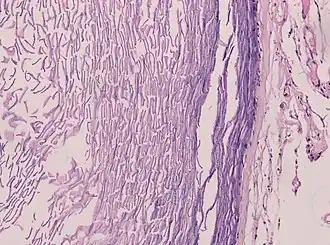

Histopathology, showing a keratinizing stratified squamous epithelium, and a lumen containing keratin flakes

Histopathology, showing a keratinizing stratified squamous epithelium, and a lumen containing keratin flakes -

Histopathology showing epithelium and lamellated keratin (left)

Histopathology showing epithelium and lamellated keratin (left)